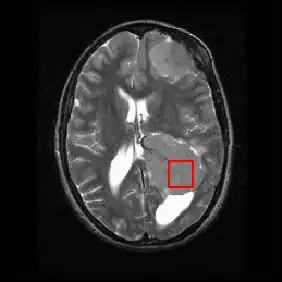

Neuroimaging contains a variety of techniques to directly or indirectly image of the structure, function/pharmacology of thenervous system. It is a relatively new fields within medicine, neuroscience and psychology.[22] Physicians who specialize in the performance and interpretation of neuroimaging in the clinical setting are neuroradiologists.

Neuroimaging is classified into two categories:

- Structural imaging, which deals with the structure of the nervous system and the diagnosis of gross (large scale) intracranial disease (such as tumor), and injury.

- functional imaging for diagnosing metabolic diseases and lesions on a finer scale (such as Alzheimer's disease) and for neurological and cognitive psychology research and building brain-computer interfaces.

| Imaging Modality | Technique | Advantage | Comparison | Image |

|---|---|---|---|---|

| General radiography | Passes electromagnetic radiation(x-rays) through body which either is absorbed by dense objects(eg.bones) or passes through to a detector on the other side of the body, creating an image | Rapid, cheap, nonvasive | minor radiation exposure | |

| CT | Passes x-rays through the body while the detector and x-ray generator rotate around the body, generating various images/slices of the body in each plane | Rapid,noninvasive | Radiation Exposure | |

| fMRI | Tracks blood flow and oxygen levels which proper neuronal activity;often superimposed on structural MRI slices for orientation; can be linked in time with MMG | Noninvasive, no radiation injection, or ingestion required | Blood flow/oxygen depend on the cardiovascular level response; results in temporal delay between stimulus and output | |

| MRI | Uses magnetic field and radio waves to create images of variably aliened and misaliened hydrogen ion in the tissue | Noninvasive, precise, no radiation | Expensive, no permission in patients with metal biomedical implants or clips/stents or severe clastrophobia |